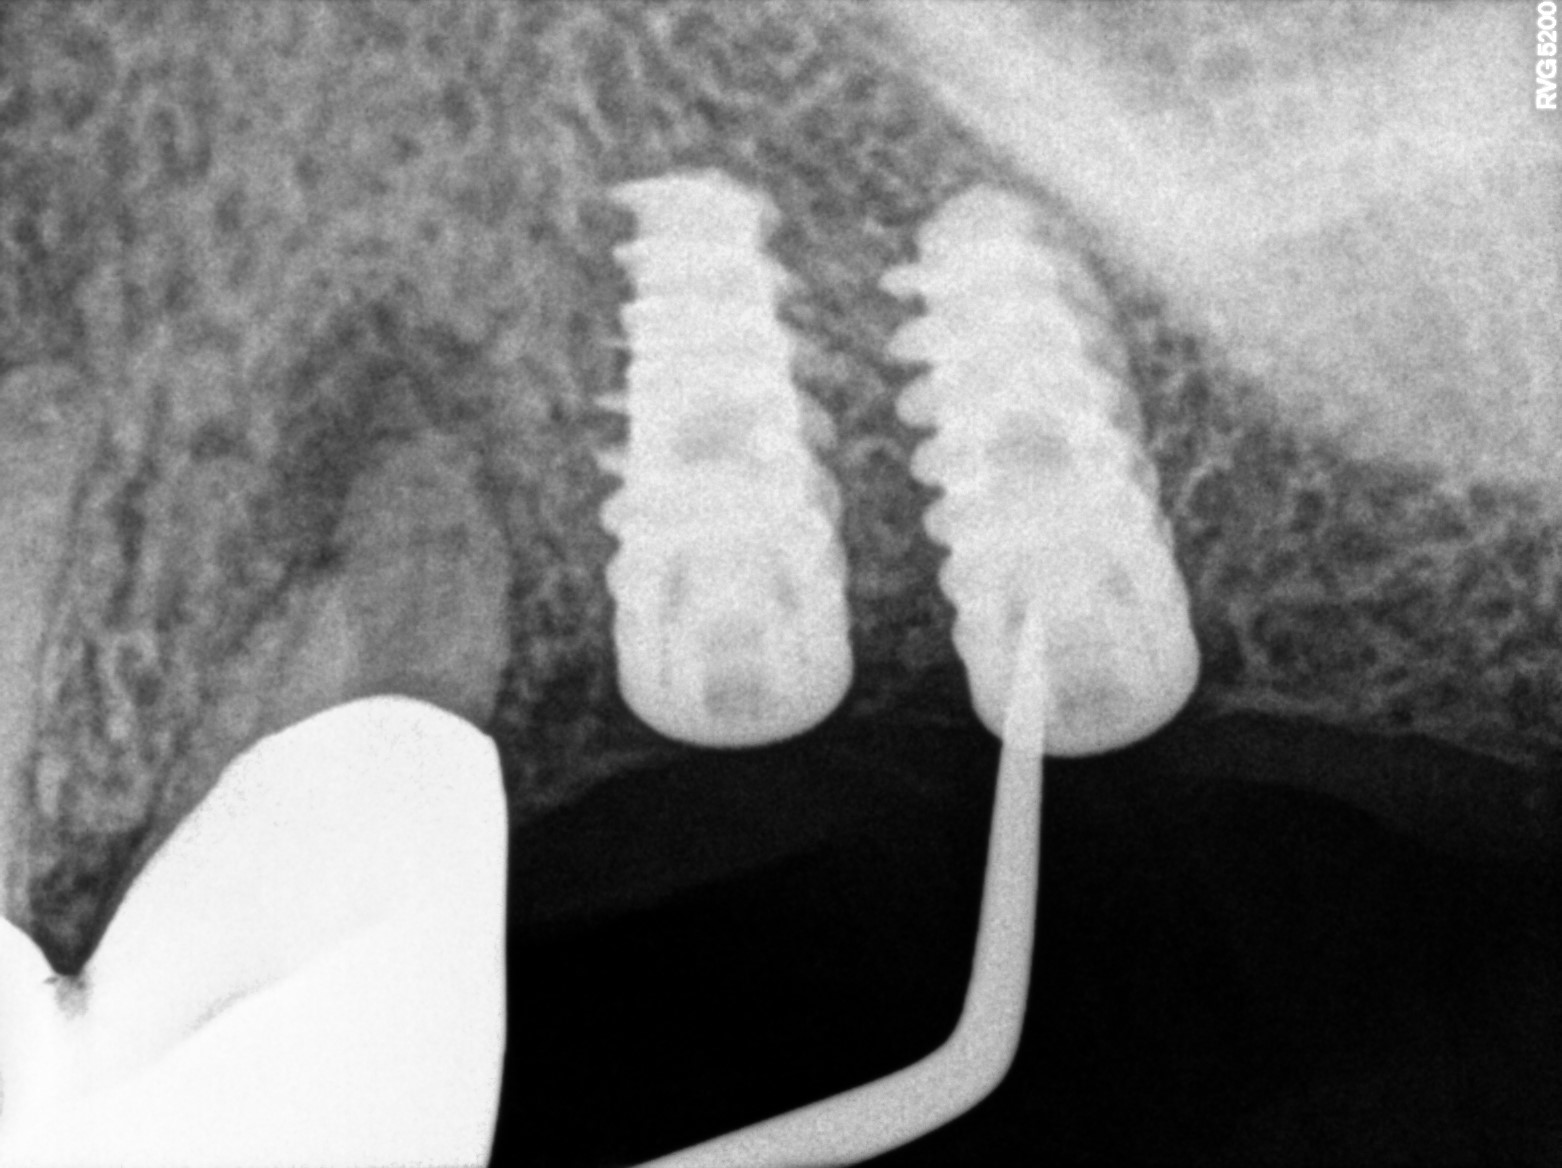

Dental Radiographs FHIR: DocumentReference · LOINC 24641-7

R66.jpg

24641-7